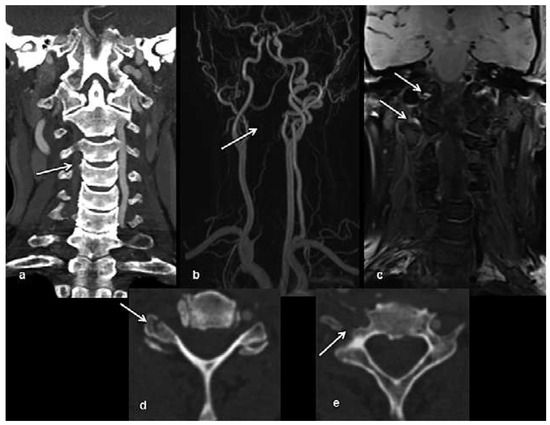

Head and brain trauma: general aspects and neuroimaging

by Johanna Maria Lieb, Christoph Stippich and Meritxell Garcia

Swiss Arch. Neurol. Psychiatry Psychother. 2015, 166(8), 279-292; https://doi.org/10.4414/sanp.2015.00374 - 1 Jan 2015

In this article the general clinical aspects, imaging indications and different injury mechanisms of traumatic brain injury (TBI) are reviewed. In addition, the different imaging modalities and strategies are presented, including more specific imaging features of the various injuries. Computed tomography (CT) is the imaging modality of choice in the acute phase owing to its wide availability and short scanning time, as well as to its high sensitivity for the detection of fractures and acute bleeding. Although magnetic resonance imaging (MRI) is superior to CT in many other aspects, it plays no role in the acute phase. MRI, however, has been proven to be useful and complementary to CT in the subacute and chronic stages as well as in the case of inconclusive results on initial CT. Especially the use of standard sequences like fluid attenuated inversion recovery (FLAIR), diffusion and susceptibility weighted imaging (DWI and SWI) have been shown to increase the diagnostic potency in diffuse axonal injury, in mild brain trauma and also in more chronic stages of TBI. The use of more advanced MRI techniques such as diffusion tensor imaging (DTI), magnetic resonance spectroscopy (MRS), functional MRI (fMRI) and magnetic transfer imaging (MTI) can further complete the diagnostic evaluation and give insights into different pathophysiological processes in TBI. Full article